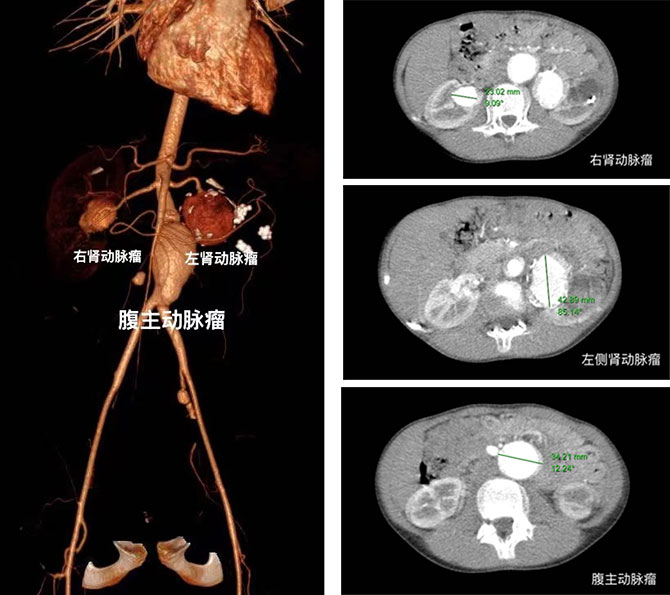

在诊断过程中,血管外科医生查体发现,小芸四肢皮肤松弛,过度伸展可牵拉至1.5cm,松手后可复原,手部小关节活动度增加。全腹CTA显示,小芸不仅手臂上有动脉瘤,还伴有腹主动脉瘤(直径34mm)、双侧肾动脉瘤(左、右直径约42 mm、23 mm,);左椎动脉瘤(直径12mm);左颈内动脉瘤(直径22mm)。动脉瘤体巨大,小芸面临着瘤体破裂危及生命的风险,急需手术干预。但诊断尚未明确,难以开展后续治疗。

2022年5月11日,血管外科王劲松教授主刀,泌尿外科刘久敏教授、血管外科连继洪副主任医师协助,为小芸实施第一期手术。因左肾动脉瘤体管壁菲薄且部分明显硬化,吻合条件差,遂放弃自体肾移植,最终行“腹主动脉瘤切除伴人工血管置换术+左肾切除术”。手术顺利,不仅为小芸解决了腹主动脉瘤随时破裂的生存风险,还体现了我院血管外科在疑难病例诊断的卓越实力以及优秀的手术能力。

小芸第一次术后,血管功能恢复良好,于2022年5月25日出院。在2022年7月13日,小芸再次入院行后续手术治疗——“肾动脉造影术+右肾动脉栓塞术”。术后小芸恢复良好出院。